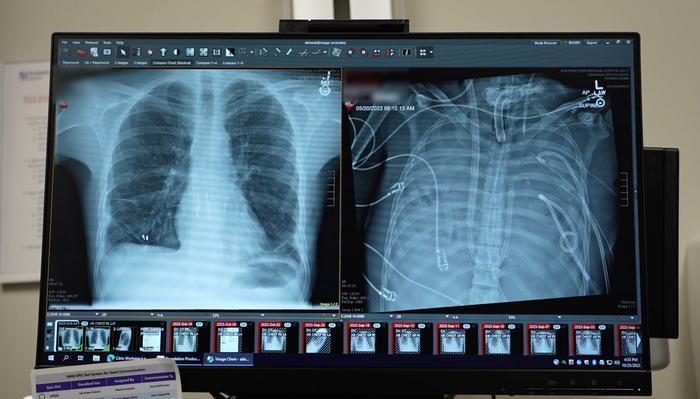

人工肺系統創造四十八小時存活奇跡